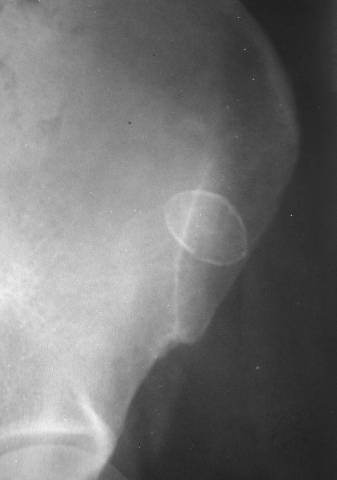

Chincona cyst